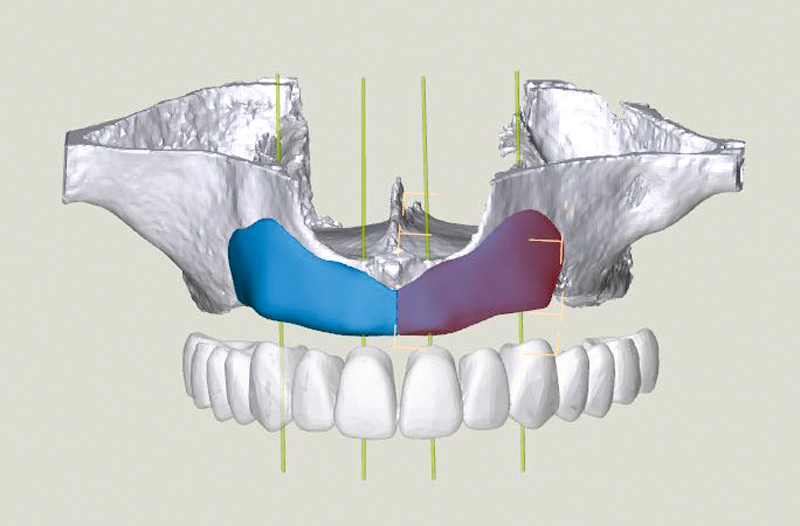

5/23 - 3D-Reconstruction of the maxilla including two maxgraft® bonebuilder blocks

Full arch reconstruction of the maxilla with maxgraft® bonebuilder - Dr. M. Erbshäuser